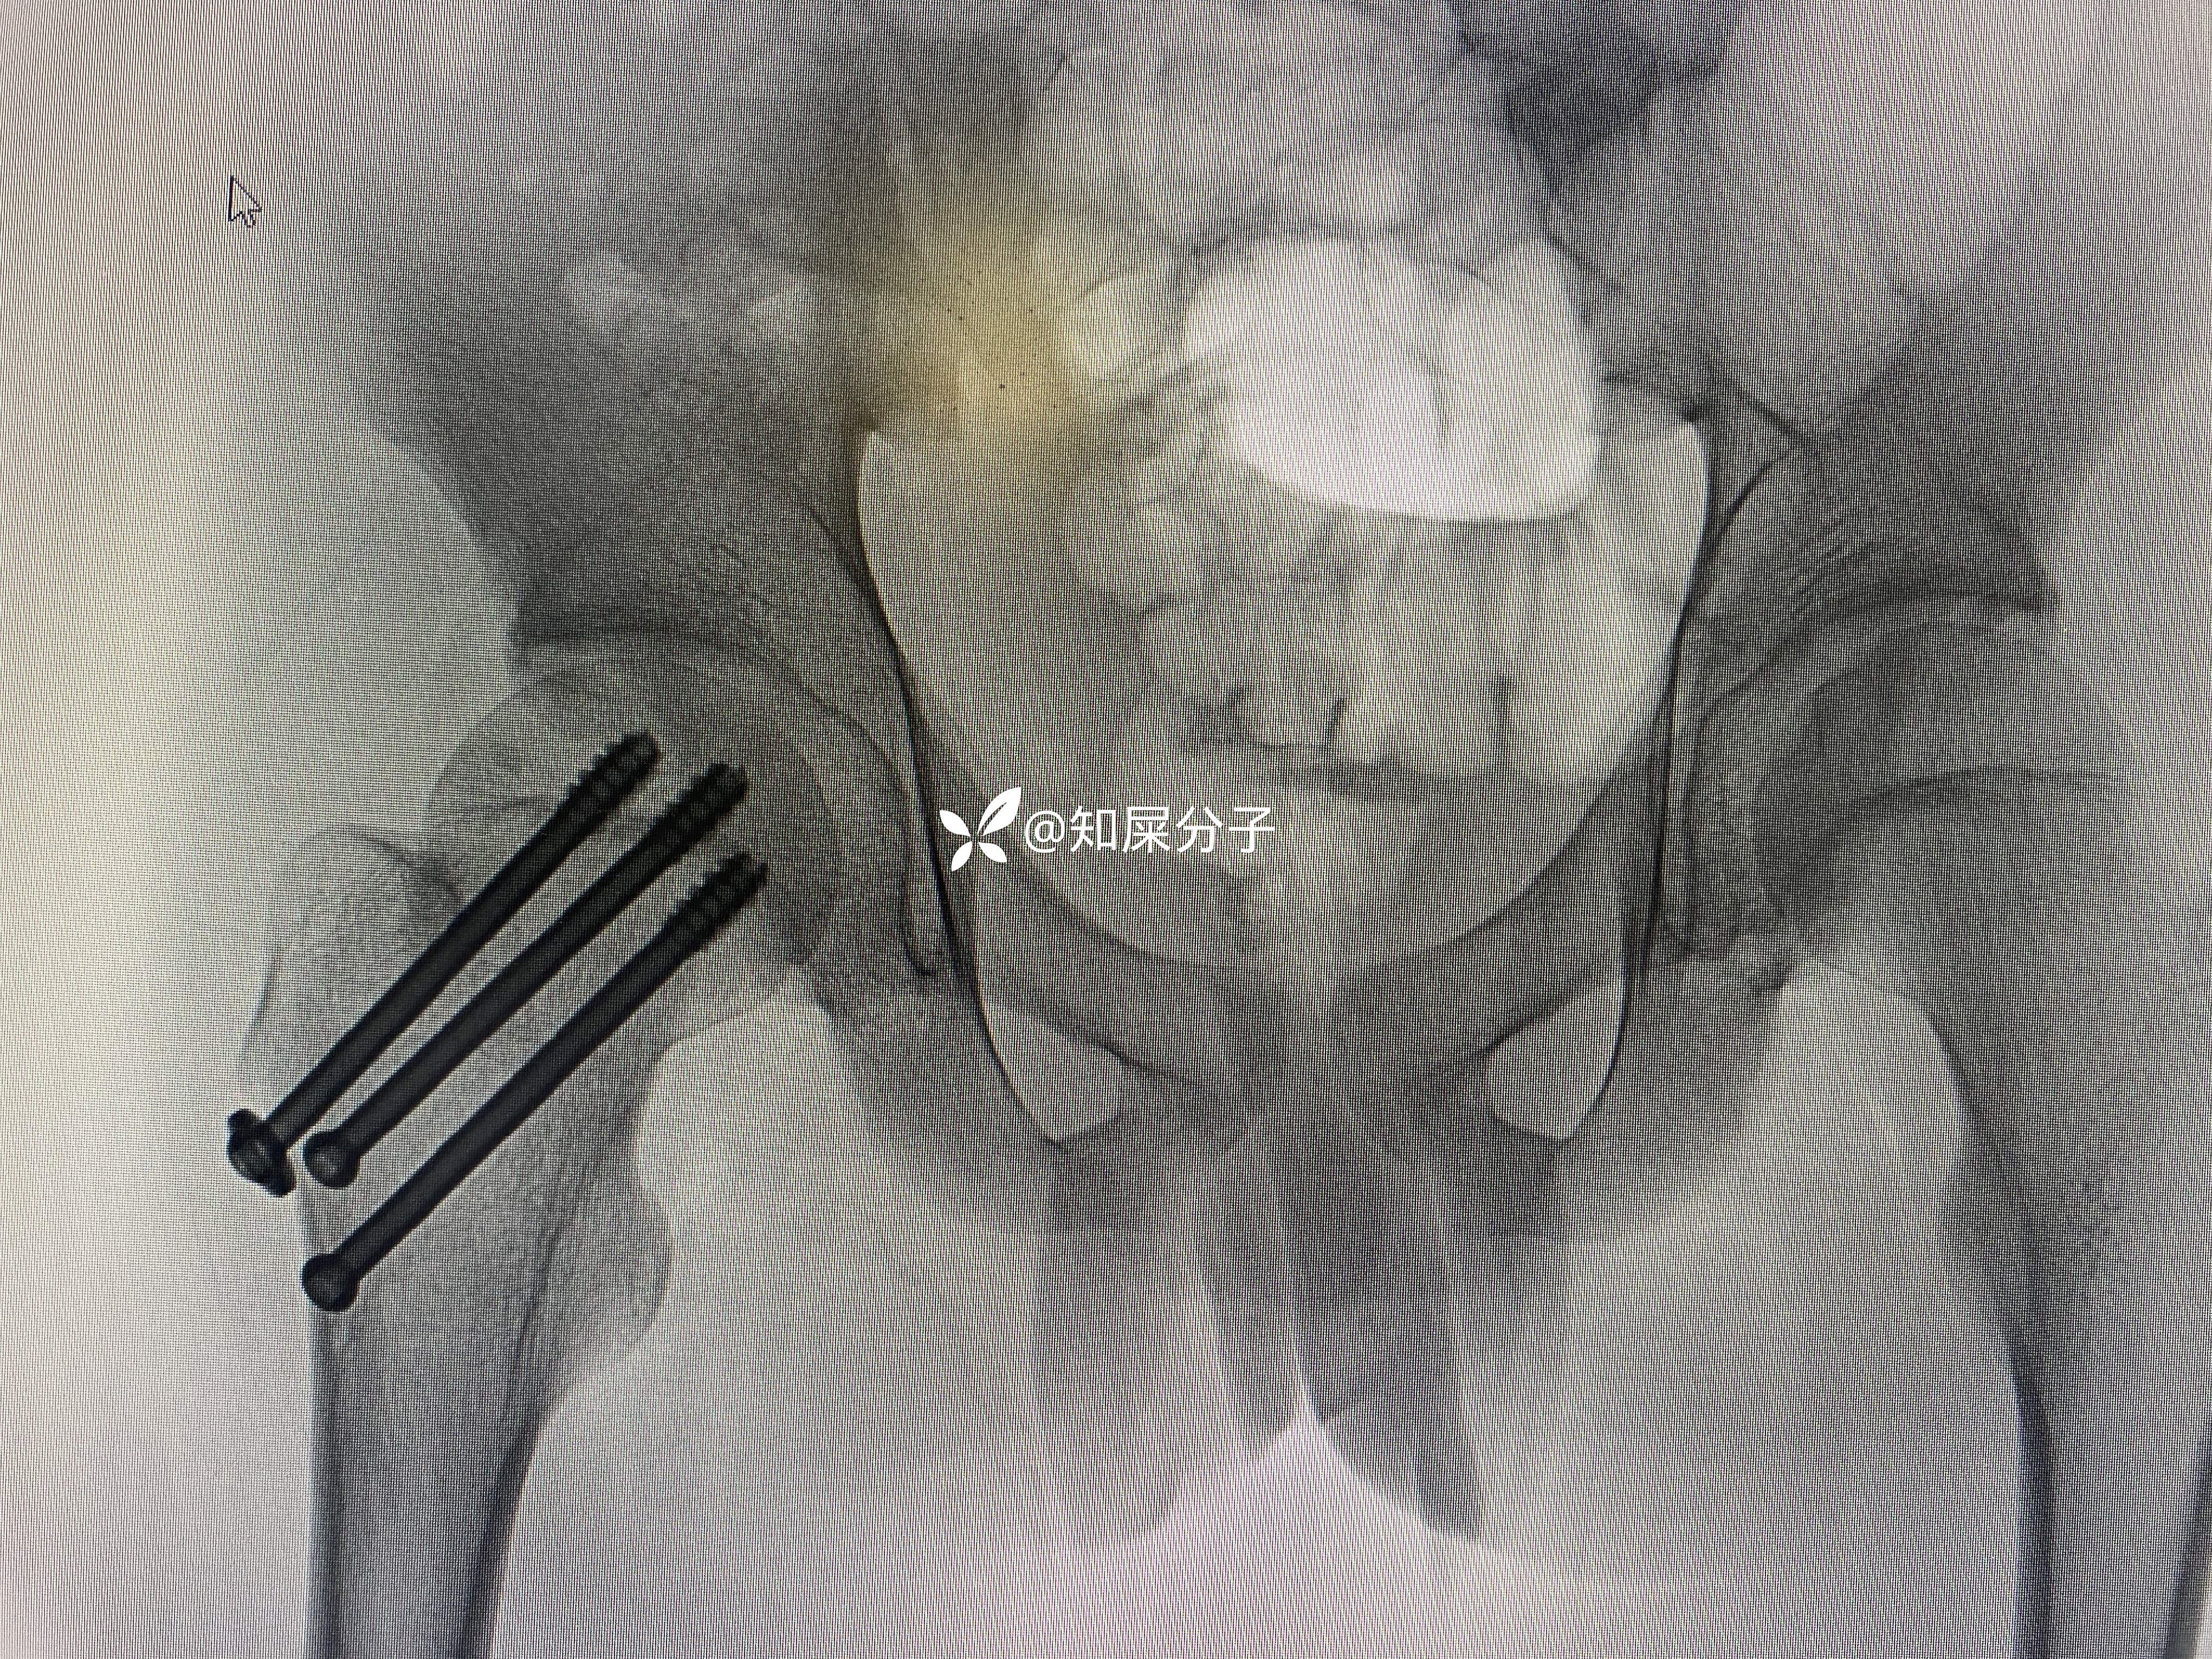

病例股骨颈骨折——青少年

男,17岁

入院后完善检查24小时内完成手术

术后如下

你是按儿童的做

按儿童的做几根钉

如何布局螺钉

还是按成人的做?